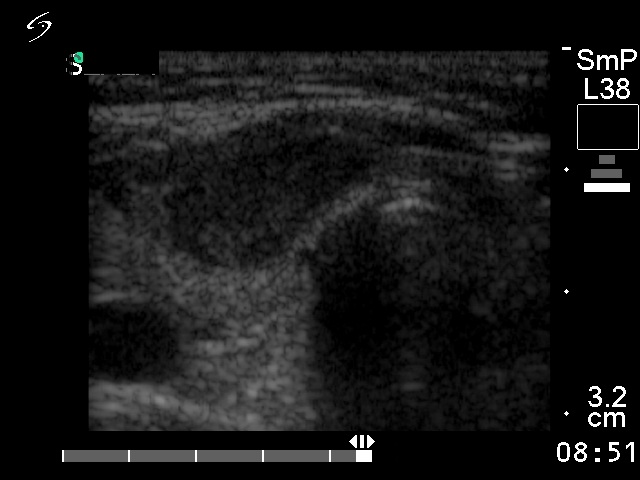

Follicular carcinoma - Case 11